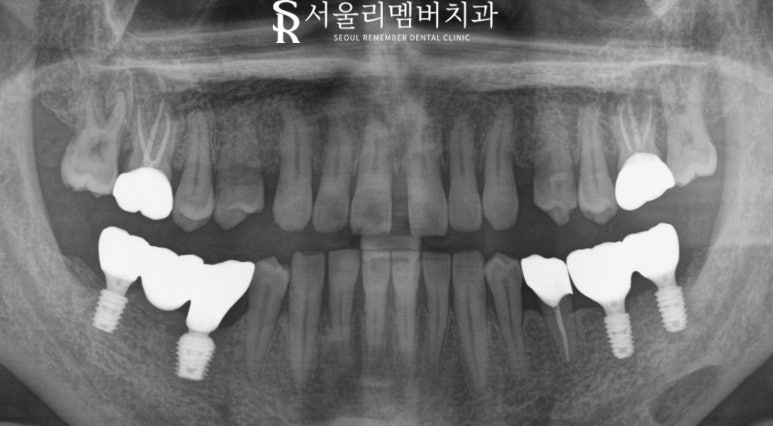

임플란트는 식립 후 뼈와 잘 붙을 수 있도록

어느 정도 회복 기간을 가지게 되는데요.

3개월 정도의 회복 시간을 가진 뒤

위에 최종 보철물을 올려주었습니다.

한 번 더 x-ray로 체크하면서

성공적인 식립이었음을 알 수 있었습니다.